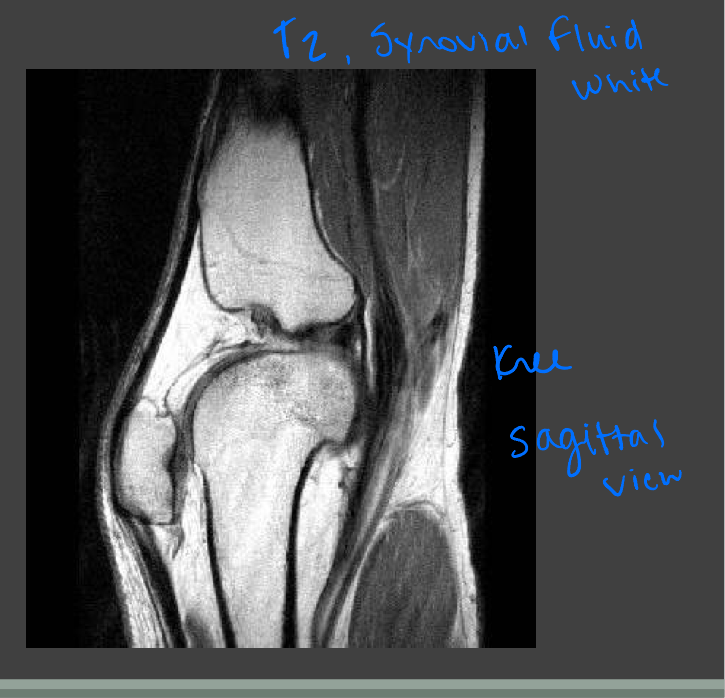

MRI: T2 weighted images

Highlights water as bright

Fat as slightly less bright

Muscle as intermediate

Brain- white matter is darker than gray matter

Joint MRI

—evaluating soft tissues injuries, such as ACL or meniscal tears